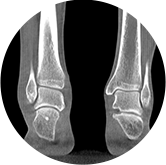

• 足踝

智能金属伪影抑制算法

关闭金属伪影校正

开启金属伪影校正